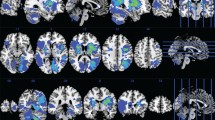

We included 2009 patients (Table 1) from the 5 cohorts (Bundang VCI: n = 758, GRECogVASC-infarct: n = 296, Hallym VCI: n = 643, PROCRAS: n = 175, STROKEDEM: n = 137) which are detailed in Supplement Table 2. The patients’ demographic and clinical characteristics (Table 1; Supplement Table 2) were typical of a hospital-based stroke population. Pre-stroke cognitive impairment (defined as an Informant Questionnaire on Cognitive Decline score > 3.38 [31]) was observed in 18.9% of the participants. Most of the imaging data were recorded in the first 2 weeks after the stroke. DWI was used most frequently for infarct segmentation. The cognitive assessment was usually performed 2 to 6 months after the stroke. The infarct distribution (Fig. 2) was similar in the two hemispheres, with a high level of brain lesion coverage: 1,556,726 of the 1,817,478 voxels (85.6%) in the Montreal Neurological Institute template were damaged in 4 or more patients. and were therefore included in the analyses. Only the distal part of the anterior cerebral artery territories, the posterobasal part of temporal lobes, the midbrain and the medulla oblongata could not be included in the analyses, due to damage observed in fewer than four patients. Furthermore, the lesion distribution was not significantly associated with age or educational level (p > 0.05 for both).